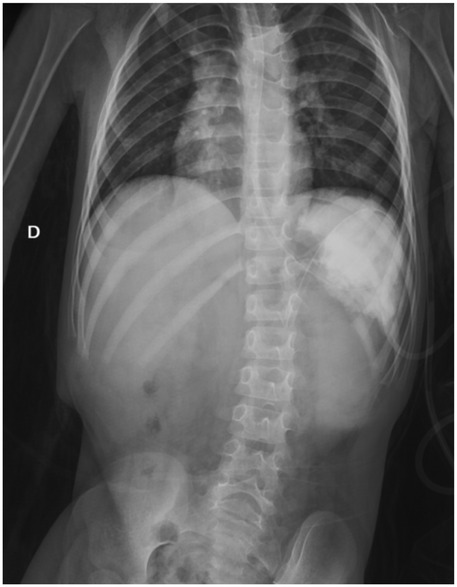

Background Acute gastric volvulus is a rare condition in children, and a delay in diagnosis may lead to gastric ischemia, perforation and even death. It is sometimes associated with wandering spleen, a condition where the spleen migrates from its normal anatomical position due to the absence of fixation ligaments. We report the first case of a patient affected by Pitt-Hopkins syndrome with simultaneous acute gastric volvulus and wandering spleen. Case report A 6-year-old male affected by Pitt-Hopkins syndrome, was urgently referred for acute abdominal pain and 24-hour history of non-bilious and non-bloody emesis. X-ray showed a massive gastric dilatation. Upper gastrointestinal series (UGI) revealed a gastric outlet obstruction. An emergency laparoscopy revealed a gastric mesoaxial volvulus with hypotonic wall with no sign of ischemia or perforation associated with a wondering spleen. Gastropexy was performed by anchoring the gastric greater curvature to the anterior abdominal wall covering the spleen in a good position in the left upper abdomen, completely covered by the gastric fundus. The patient made uneventful recovery and was completely asymptomatic. Conclusion To our knowledge, this is the first case of simultaneous gastric volvulus and wandering spleen in a patient affected by Pitt-Hopkins syndrome. Laparoscopic gastropexy is an easy procedure and combines the advantages of all surgical techniques adopted in previous eras.